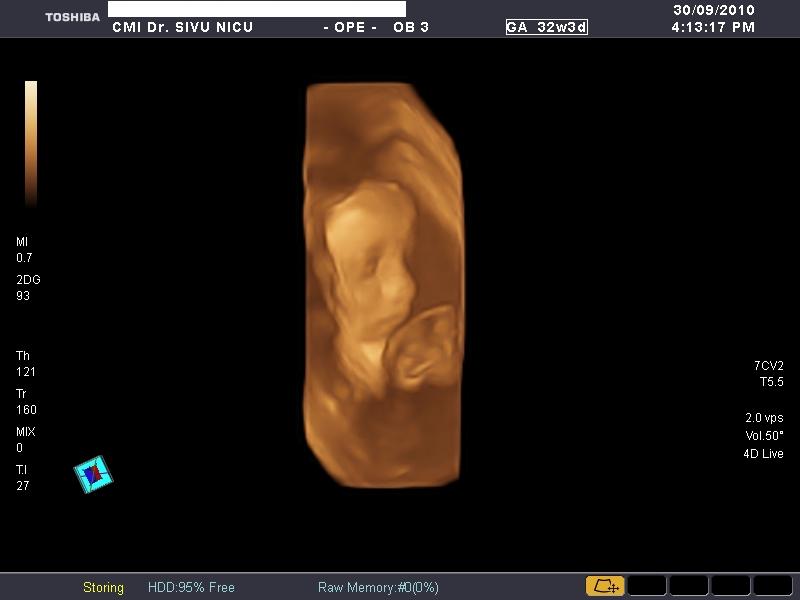

De sarcina (morfologie,biometrie,3D si 4D)

Poze realizate pe ecograful

Toshiba Applio XG